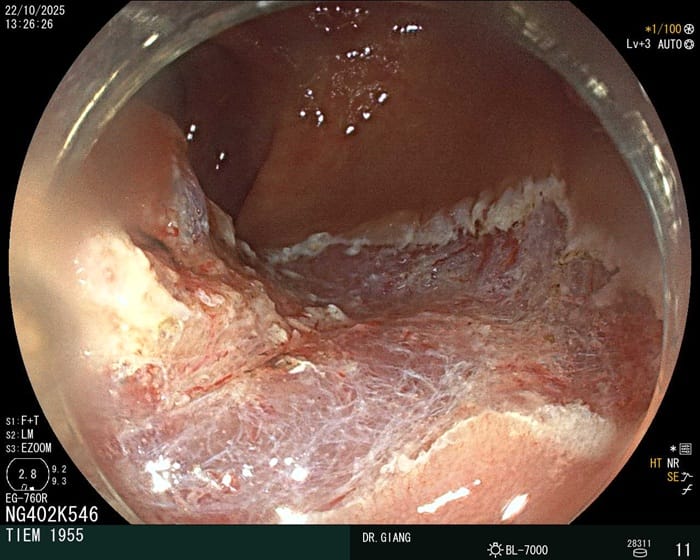

Hình ảnh viêm đại tràng bất thường

Ở người bị viêm đại tràng, sau nội soi cho thấy niêm mạc đỏ rực hoặc sậm màu, phù nề rõ và dễ chảy máu khi chạm vào. Một số trường hợp xuất hiện vết loét nông hoặc sâu, kèm theo mảng trắng, giả mạc hoặc vùng niêm mạc phồng lên do xơ hóa. Ngoài ra, dịch nhầy hoặc máu dính trên bề mặt là dấu hiệu điển hình cho thấy tình trạng viêm đã tiến triển.

Đại tràng có bờ trắng, viêm loét sau khi nội soi